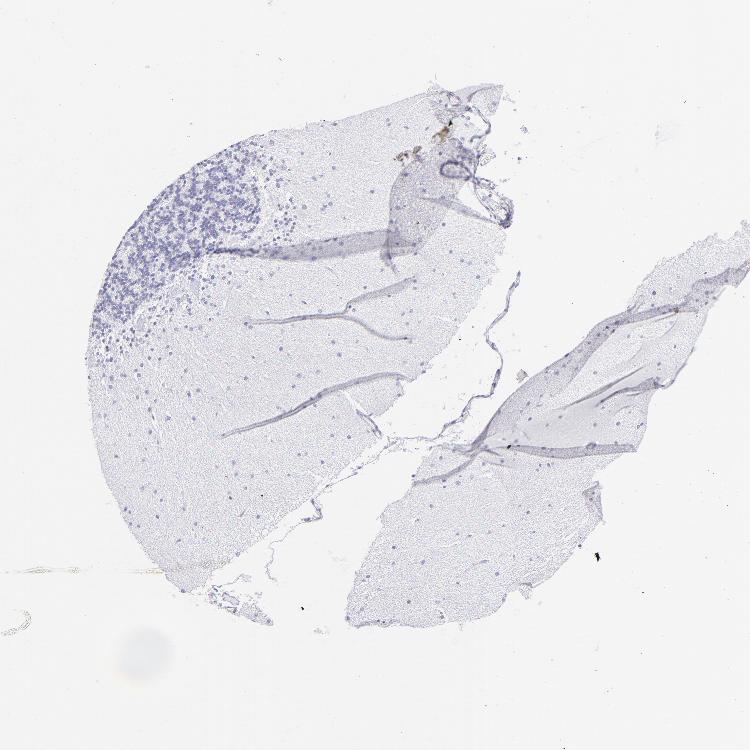

CEREBELLUM - Antibody stainingi

Antibody staining in the annotated cell types in the current human tissue is reported as not detected, low, medium, or high, based on conventional immunohistochemistry profiling in selected tissues. This score is based on the combination of the staining intensity and fraction of stained cells.

Each image is clickable and will lead to virtual microscopy that enables deeper exploration of all samples and also displays staining intensity scores, fraction scores and subcellular localization as well as patient and tissue information for each sample.

Antibody HPA009177Antibody CAB002661

Purkinje cells Not detectedNot detected

Cells in granular layer Not detectedNot detected

Cells in molecular layer Not detectedNot detected